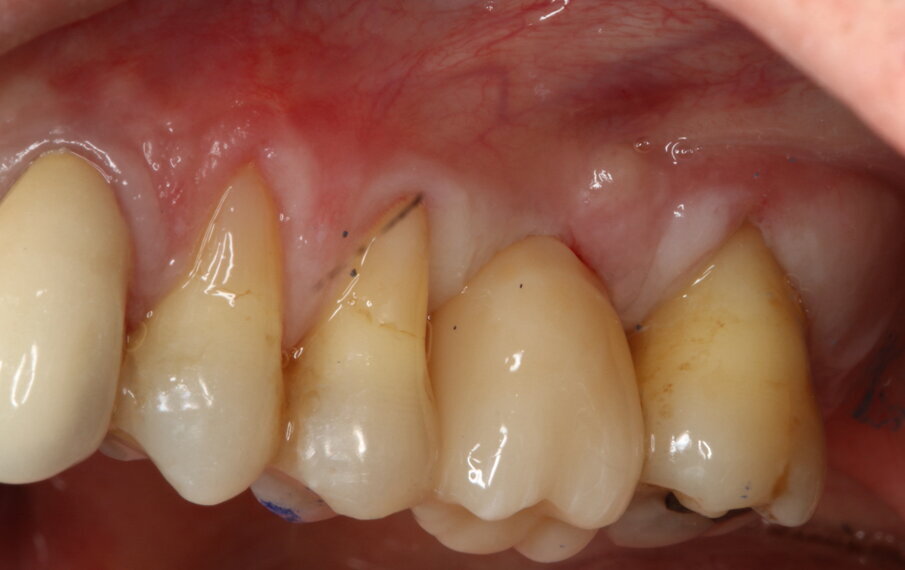

Fig. 8_Guarigione dopo 4 mesi.

Fig. 9_Guarigione dopo 4 mesi con focus sui tessuti molli perimplantari.